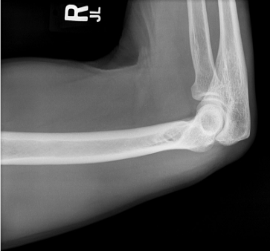

name the position

transthoracic lateral humerus

name position/projection; in what position is the beam in? what position is the patient in? is there a breathing technique present?

transthoracic lateral humerus, horizontal beam lateral, supine, yes

evaluation criteria for transthoracic lateral humerus

proximal 2/3 of humerus OR entire humerus w/ elbow joint

overlying ribs and lung marking blurred